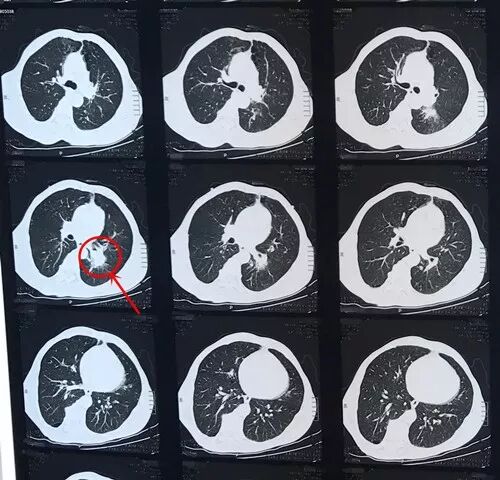

59岁的刘先生,近2个月来突然出现“间断咳嗽、痰中带血”症状,入住我院外三科,经详细检查,确诊为左下肺鳞癌。由于肿瘤较大,侵及左肺上叶支气管及肺动脉,加之病人有慢支及胸廓畸形,致使病情异常复杂。主管医师金洛伊会同外科专家组组长段跃建及科室集体讨论,结合外出进修所学技术,制定了完善的手术预案,经病人家属同意,于3月上旬为病人行胸腔镜手术。术中发现一5cm×6cm×7cm肿瘤,侵犯左肺中间干支气管,肺上叶肺动脉及上叶支气管开口极难分离。经过6小时努力,在完整切除肿瘤成功保留肺上叶的同时,顺利完成肺支气管和肺动脉成形术,有效解除了病人的病痛,目前病人已康复出院。

术前CT显示:左下肺占位